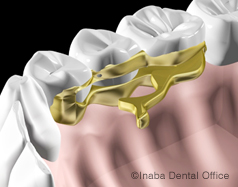

近所の歯科医院で部分入れ歯を作りましたが、上顎の裏側に金属の板が取り付けてあり、厚みもあるので違和感を覚えます。この金属の板を外すことはできますか?

当院では特殊な型のパラタルバー(金属の板)を取り付け、

またインプラントと併用することでも違和感を軽減できます。

上顎の裏側にある金属の板は"パラタルバー"という連結装置で、両側の入れ歯を連結して残っている歯への負担を軽減する役割があります。

中途半端な位置に取り付けてしまうと、違和感が強くなり、発音や食物を飲み込むときに邪魔になります。

当院のご提案(1)

当院では、入れ歯を安定させるために上顎の裏側(口蓋)を金属でカバーする場合がありますが、特殊な型のパラタルバーを取り付けますので、会話や食事の際に感じる違和感をできるだけ軽減することができます。

当院のご提案(2)

また、部分入れ歯とインプラントを併用することで、パラタルバーや金属床の面積を小さくすることができます。

当院のご提案(3)

歯の本数や欠損の場所によっては、「トーションバー」という特殊な連結装置を使うことで、口蓋部を金属床で大きく覆わずに済む設計も可能です。

「トーションバー」を使った症例(上顎)